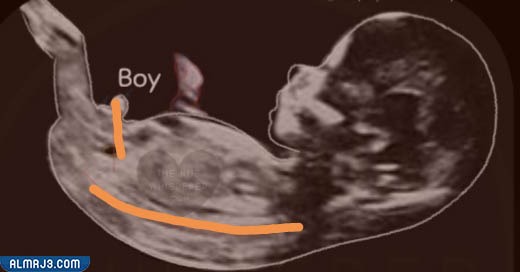

سونار الولد في الشهر الثالث

في حال كان اتجاه النتوء التناسلي، نحو الأعلى باتجاه الرأس، وتكونت زاوية تزيد عن 30 درجة، بالنسبة للعمود الفقري، فمن المتوقع أن يكون المولود ذكرًا، كما سيبدأ النتوء التناسلي، بالتمايز إلى ما يشبه كيس الصفن (بالإنجليزية: Scrotum)، والقضيب (بالإنجليزية: Penis)[4]، وبالنظر إلى صورة السونار في الأسفل، يمكن تمييز الاختلاف بينها وبين صورة سونار البنت.